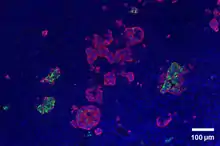

Through different microscopy techniques, the structural related details of PP cells have been able to be better understood. This is inclusive of how big they are, what their cellular membranes look like, the proteins associated with them, and even their size. PP cells are elongated cells. Another one of these details can be noted in insulins secretory granules, or container like buds, that store insulin within a cell. In PP cells, the size of the insulin granules are smaller and spherical and similar to those in alpha cells. This is noted in human PP cells, but different animals have been shown to have different sized granules compared to humans, like rodents. In cats and dogs, PP cells have large granules.[8] In rats, PP cells have few granules, similar to humans. In dogs, some PP cells are located in the walls of the antrum of the stomach.[3]